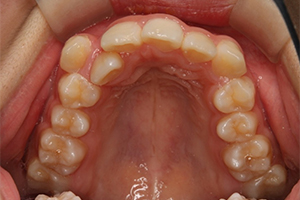

矯正治療のCASE 05

Before

After

-

- 主訴

- 歯並びがガタガタしていて清掃しにくい

- 治療内容

- ラビアル矯正(表側)

抜歯あり

- 治療費用

- 88万円~(税込)

- 治療期間

- 20か月

【リスク・副作用】

歯の痛み、口内炎、歯磨きがしにくいことによるむし歯や歯周病のリスク、歯根吸収や歯の変色、後戻りなどの副作用があります。